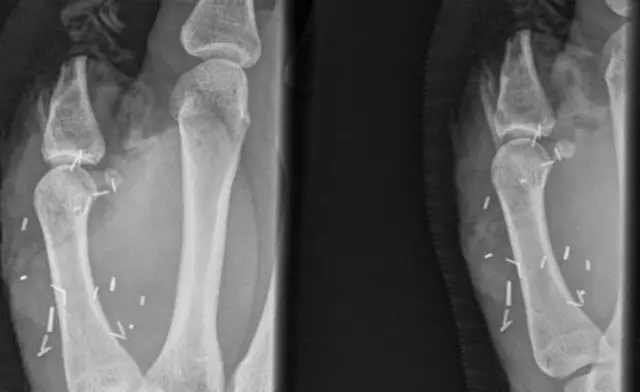

ที่มาของภาพ, An X-ray showing Mr Mitchell's injured handImage c

แซค มิตเชล วัย 20 ปี เกษตรกรฟาร์มปศุสัตว์ในเขตชนบททางตะวันตกของออสเตรเลีย ถูกพ่อวัวเตะมือของเขาอัดเข้ากับรั้ว ขณะทำงานอยู่ในฟาร์มเมื่อเดือน เม.ย.ที่ผ่านมา จนเป็นเหตุให้นิ้วโป้งของมือข้างขวาขาด หลังเกิดเหตุแพทย์พยายามผ่าตัดเพื่อทำการต่อนิ้วโป้งให้เขาถึง 2 ครั้ง แต่ไม่สำเร็จ ก่อนที่แพทย์จะเลือกใช้วิธี ผ่าตัดนำเอานิ้วโป้งที่เท้าข้างขวาของหนุ่มออสเตรเลียรายนี้ มาต่อแทนที่นิ้วโป้งที่หลุดออกไป